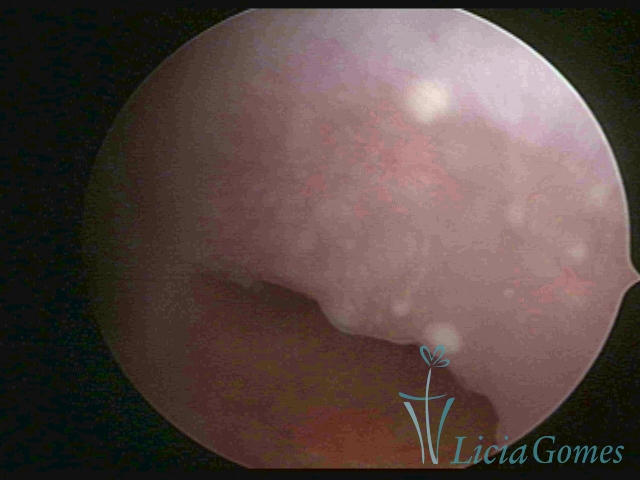

Primeira porção ou setor proximal ou setor inferior:

Durante a fase proliferativa, encontramos muco claro e cristalino pouco aderente à óptica. As criptas e as papilas apresentam-se um pouco edemaciadas e vascularizadas, micro vesicular, lembrando cachos de uva.